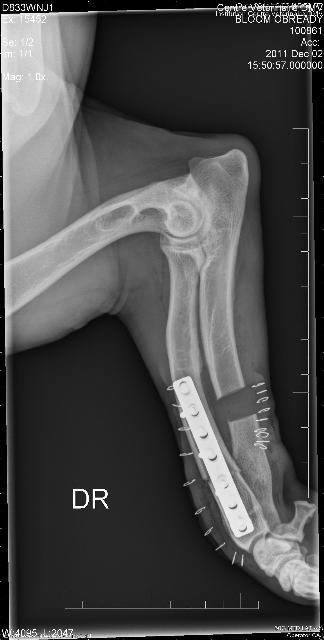

Her radius curvus syndrome was addressed, a bloat survivor and nothing ever held her back!